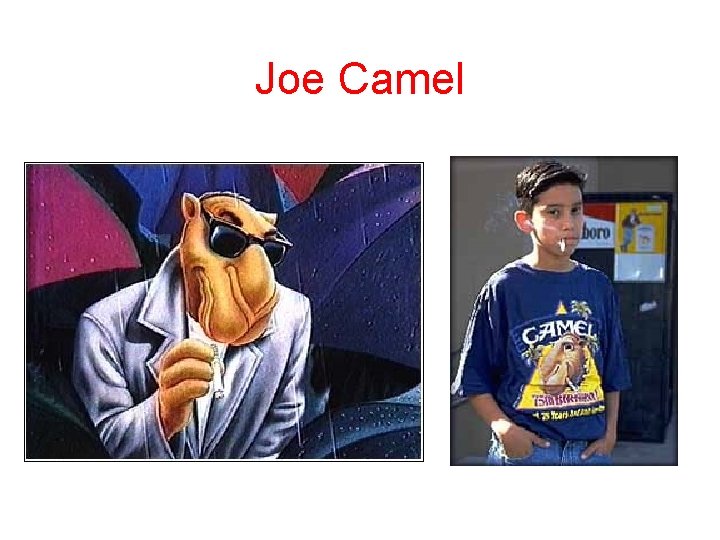

The Cool Kids

Joe Camel